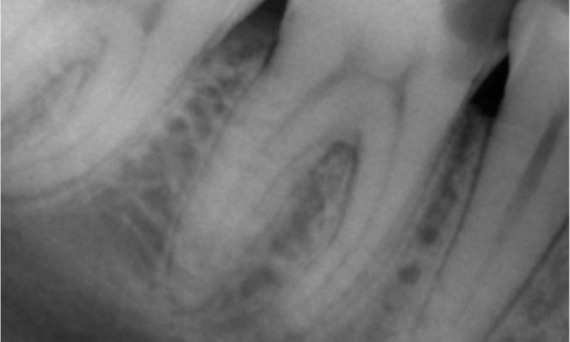

Antes: Tras el examen, hubo una lesión de caries relacionada con el primer molar inferior derecho. El examen radiográfico reveló la proximidad de la lesión a la bocina pulpar y, al combinarla con la queja principal, se concluyó un diagnóstico final de pulpitis irreversible crónica.

Después: La cavidad de acceso se realizó de la manera más conservadora posible. TruNatomy fue el sistema de elección debido a la edad del paciente joven. Necesitábamos preservar la dentina tanto como fuera posible para aumentar la capacidad del diente y así superar la carga oclusal y aumentar la longevidad de la restauración final.